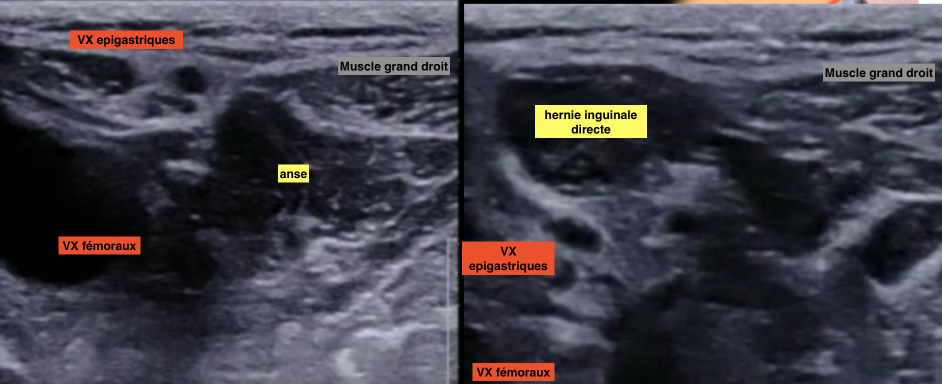

Hernies inguinales

Technique

- Sonde pointe un peu vers le nombril

- Aligner VX fémoraux - VX epigastriques - Droit abdomen

- Repères anatomiques:

- Vx épigastriques inférieurs (les suivre depuis en haut si doute) = 1 artère 2 veines

- Cordon spermatique

- Muscle droit de l’abdomen

Coupe standard

Hernie inguinale indirecte

Hernie inguinale directe